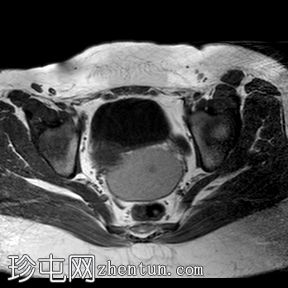

轴位

T1加权像

阴道明显扩张,T1加权像呈中高信号,T2加权像呈高信号,耻骨联合下方可见一小局灶性隆起。

盆腔内可见少量游离液体。